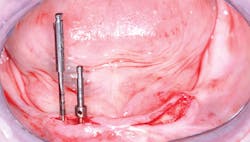

Figure 1: For a patient such as this edentulous person, it is nearly impossible to determine the potential bone quality and quantity without several diagnostic aids and adequate radiographs described in this article.

Figure 2: On exposing the bone on the patient in Figure 1 and making an osteotomy, the density of the bone becomes apparent to the clinician who is placing the implant, and density relates directly to the time needed to attain implant stability.